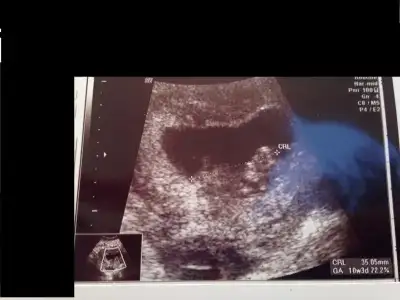

Bizim daha yeni, şuan 10+3 günümüz. 9+6 iken aşağıdaki şekildeydi durumumuz. Herhangi bir yorum yapabilen olurmu acaba :)

selam kızlar. Bugün kontrolümüz vardı minnağım kocaman olmuş el ayak sallar hale gelmiş :) 10+1 dik ama 2 gün önde gidiyor benimki 1 aydır o yüzden 10+3 ölçüyor usg. Fotoda nub gözükecek şekilde çıkmamış ama ben yinede bir şansımı deniyim kızlardan bir tahmin almaya çalışıyım dedim. Doktorum cinsiyet tahmini için 1,5 ay sonra dedi kim beklicek okadr çatlarım ben :) Bakın bakalım bişiler görebilecekmisiniz canlarım :16:

Bence bebisin prenses canim haftasi küçük olduğu için değişme ihtimali yuksek ama nubu net kiz